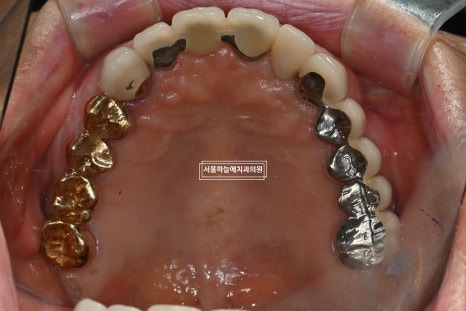

처음 내원 시 상태

처음 내원 당시 엑스레이와 구강 상태를 보면

앞니는 파절되어 있었고

아래 어금니가 없는 기간이 길어

위 치아와 잇몸이 맞닿을 정도로 공간이 부족,

아래 앞니 역시 심하게 마모된 상태였습니다.